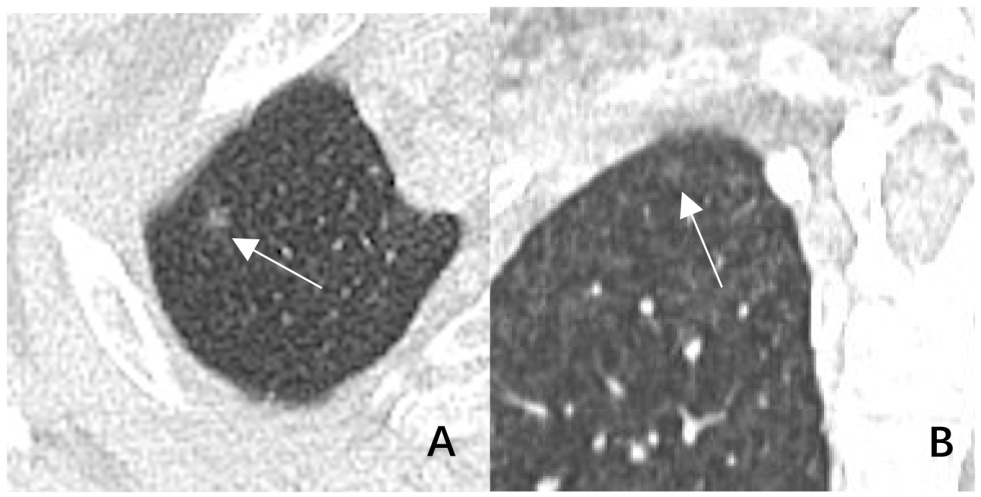

1) 右肺上叶肺尖部直径约3 mm pGGN (见图1),与肋骨轻度重叠,表现为极低密度磨玻璃影,AI未识别病灶(A,轴位,箭头;B,冠状位,箭头)。

Figure 1. Typical image of AI missed diagnosis

1. AI 漏诊典型图像